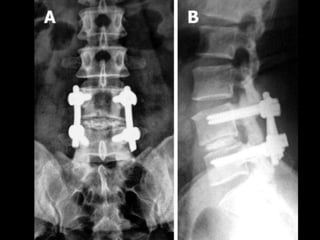

SPINAL FUSION

INDICATIONS:

• Young patients with signs of spondylolisthesis

• Post laminectomy who show instability

• Advanced intervertebral arthritis

• Need to return back to heavy manual work.

TREATMENT